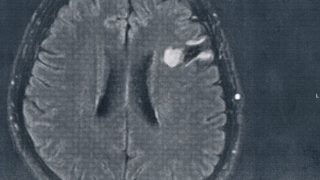

GLIOMA:手術後138ヶ月目の検査

手術から11年が経過した。半年ごとの定期検査です。検査概要びまん性星細胞腫グレード2(悪性転化しやすい腫瘍)MRI検査: 造影剤なし / 造影剤あり造影剤ありの場合:4時間前から絶食し、MRIの1時間前に血液検査を済ませる。診断結果前回のM...